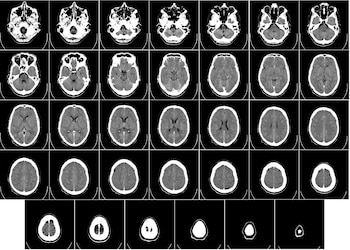

Otro desafío al apuntar memorias únicas para la edición es que, con una rara excepción, las firmas neuronales de incluso las memorias recientes son complejas y se pueden distribuir por todo el cerebro, por lo que no es práctico identificarlas mecánicamente y apuntarlas para su edición.

Los conjuntos neuronales que representan recuerdos únicos están activos en ciertos momentos y, por lo tanto, pueden ser vulnerables a la edición durante estos períodos específicos. Uno de esos momentos es durante la consolidación inicial de los recuerdos, que es un proceso gradual de transformación y estabilización que implica reactivaciones neuronales recurrentes de la memoria, tanto mientras la persona está despierta como dormida.

Los estudios de neuroimagen del control de la memoria muestran que estas técnicas comprometen los circuitos cerebrales prefrontales que son típicos del control y podrían ser la base de la inhibición o la supresión.

Estos estudios también muestran una reducción de la actividad dependiente del nivel de oxigenación de la sangre en el hipocampo y cambios en un marcador del hipocampo del neurotransmisor GABA (ácido γ-aminobutírico), que indica la inhibición de los procesos de recuperación del hipocampo. Estos hallazgos son consistentes con la inhibición de la consolidación del hipocampo, que puede promover el olvido y la edición de la fuerza de la memoria.